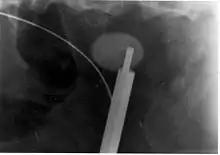

Where a CT scan is unavailable, an intravenous pyelogram may be performed to help confirm the diagnosis of urolithiasis. This involves intravenous injection of a contrast agent followed by a KUB film. Uroliths present in the kidneys, ureters, or bladder may be better defined by the use of this contrast agent. Stones can also be detected by a retrograde pyelogram, where a similar contrast agent is injected directly into the distal ostium of the ureter (where the ureter terminates as it enters the bladder).[60]

Ureteroscopy has become increasingly popular as flexible and rigid fiberoptic ureteroscopes have become smaller. One ureteroscopic technique involves the placement of a ureteral stent (a small tube extending from the bladder, up the ureter and into the kidney) to provide immediate relief of an obstructed kidney. Stent placement can be useful for saving a kidney at risk for postrenal acute kidney failure due to the increased hydrostatic pressure, swelling and infection (pyelonephritis and pyonephrosis) caused by an obstructing stone. Ureteral stents vary in length from 24 to 30 cm (9.4 to 11.8 in) and most have a shape commonly referred to as a "double-J" or "double pigtail", because of the curl at both ends. They are designed to allow urine to flow past an obstruction in the ureter. They may be retained in the ureter for days to weeks as infections resolve and as stones are dissolved or fragmented by ESWL or by some other treatment. The stents dilate the ureters, which can facilitate instrumentation, and they also provide a clear landmark to aid in the visualization of the ureters and any associated stones on radiographic examinations. The presence of indwelling ureteral stents may cause minimal to moderate discomfort, frequency or urgency incontinence, and infection, which in general resolves on removal. Most ureteral stents can be removed cystoscopically during an office visit under topical anesthesia after resolution of urolithiasis.[114] Research is currently uncertain if placing a temporary stent during ureteroscopy leads to different outcomes than not placing a stent in terms of number of hospital visits for post operative problems, short or long term pain, need for narcotic pain medication, risk of UTI, need for a repeat procedure or narrowing of the ureter from scarring.[115]